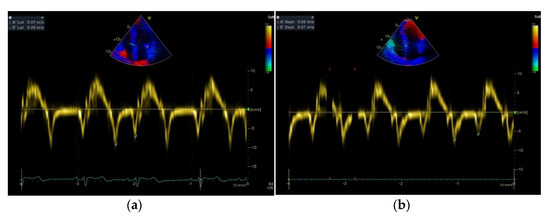

| E/E’ aver | 9.24 ± 1.42 a,b | 7.00 ± 0.9 | 5.76 ± 0.8 |

| Septal E’ velocity (cm/s) | 6.2 ± 0.70 a,b | 10.0 ± 0.9 | 11.1 ± 0.82 |

| Septal A’ velocity (cm/s) | 5.6 ± 0.6 | 6.7 ± 0.6 | 7 ± 0.7 |

| Lateral E’ velocity (cm/s) | 9.1 ± 0.6 a,b | 13.4 ± 0.5 | 14 ± 0.5 |

| Lateral A’ velocity (cm/s) | 7.1 ± 0.5 | 7.9 ± 0.6 c | 8 ± 0.7 |